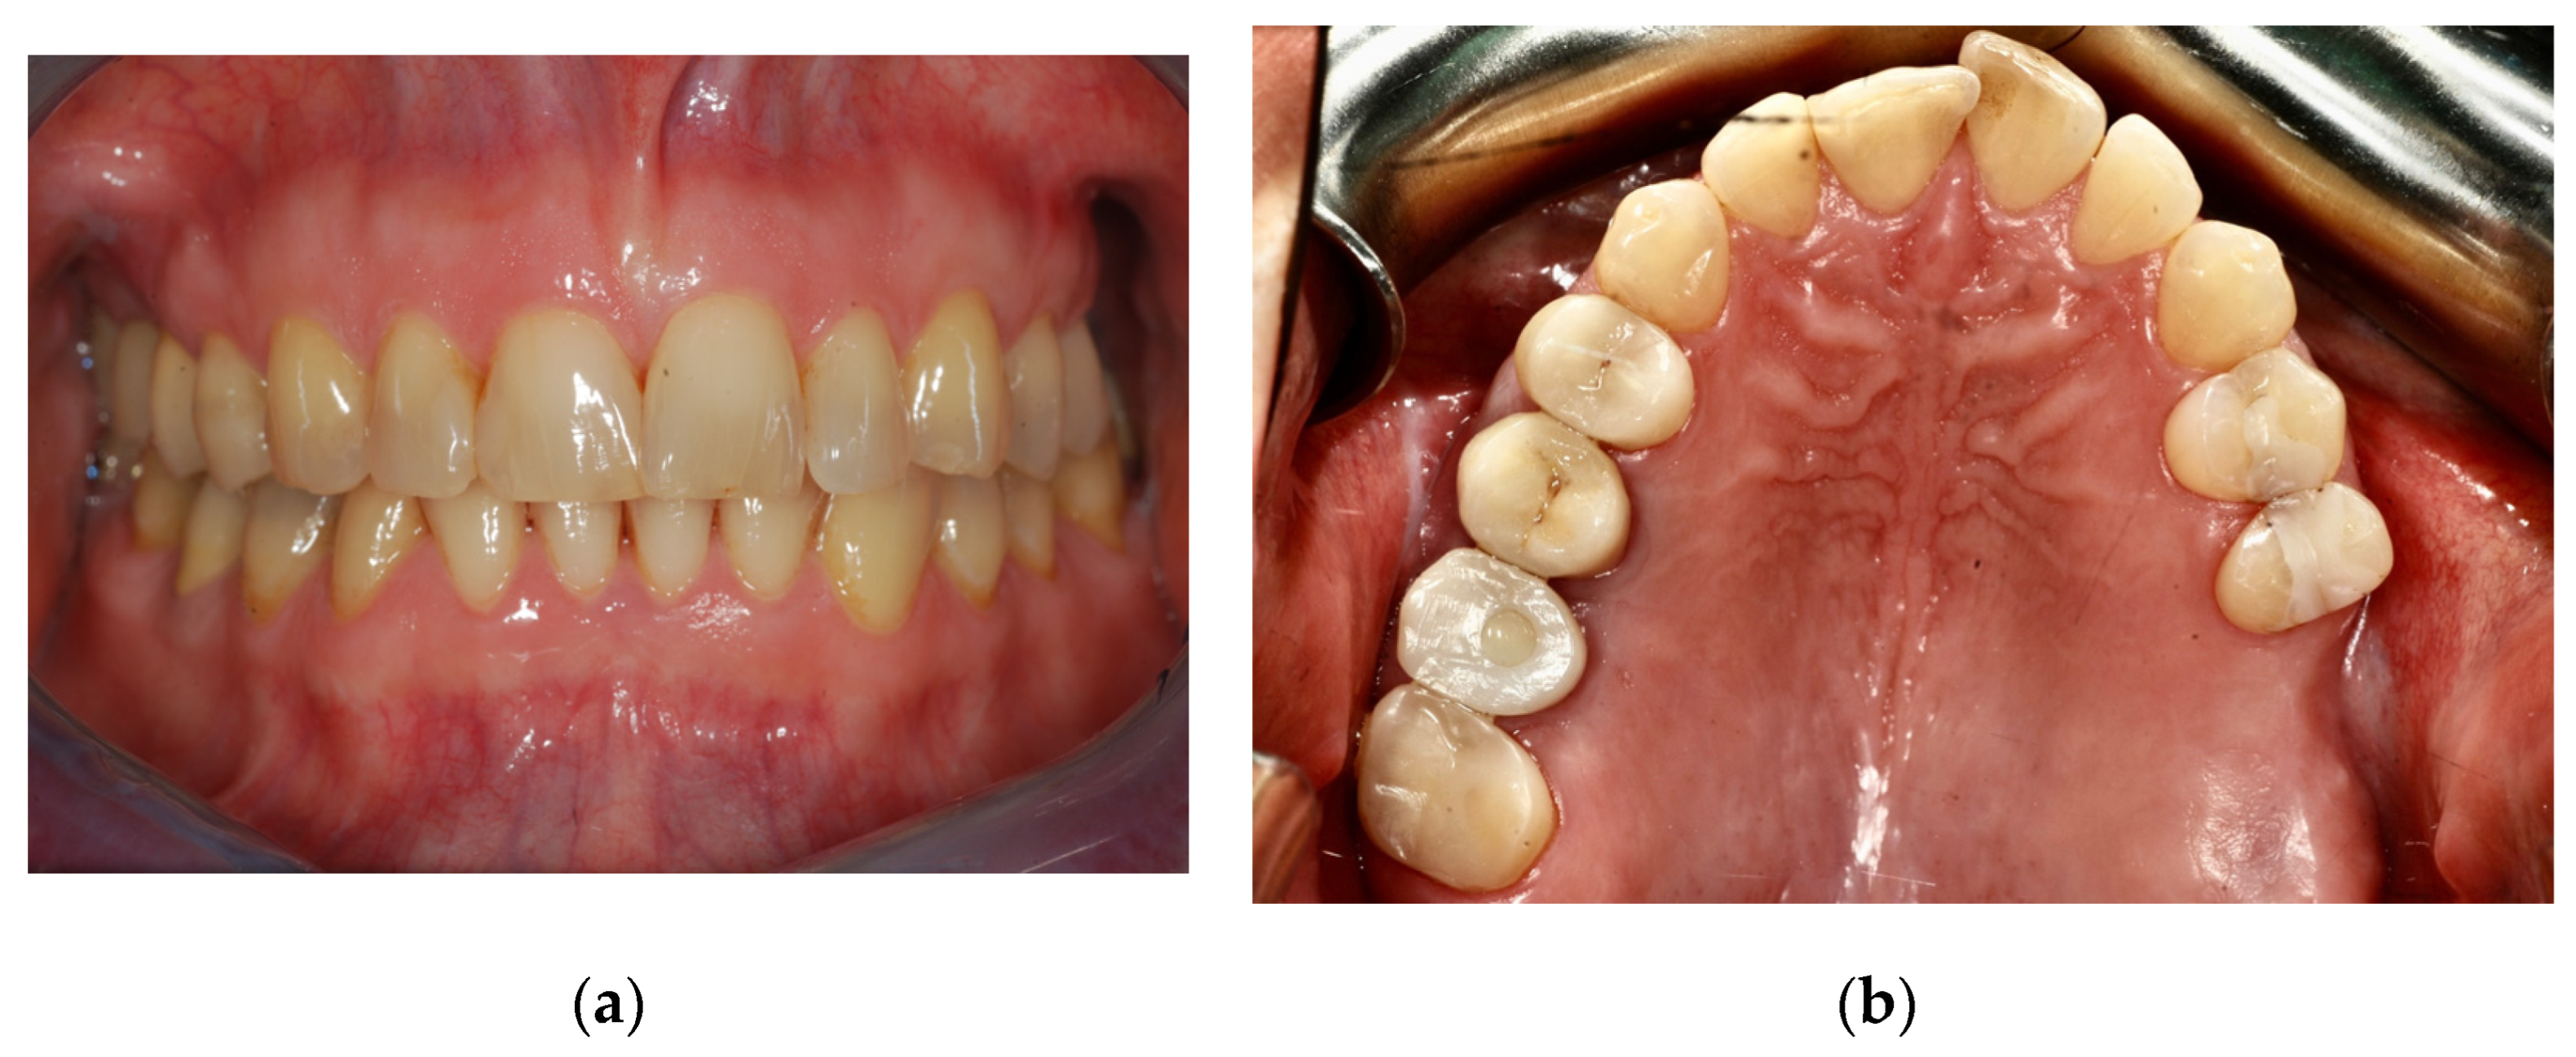

We report a case of a 45-year-old woman in general good health, not taking medications, who presents for prosthetic rehabilitation of the left upper jaw (Figure 1).

Figure 1.

Preoperative records: (a) frontal view; (b) occlusal view.